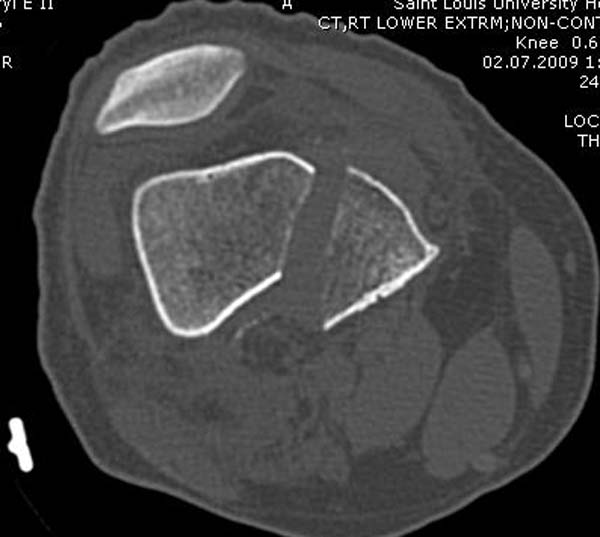

[Ortho] Нелеченный перелом Hoffa

Здесь представлены различные варианты фиксации перелома, а также снимки

комбинации перелома с повреждением хряща (12-19). Пластика хряща

OsseoFit и установка custom made plate.